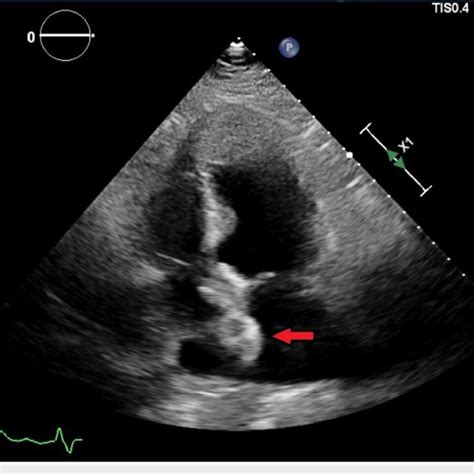

researchgate.net

A 25-mm Amplatzer PFO occluder device visualized on …

Bubble study showing significant right to left shunti…